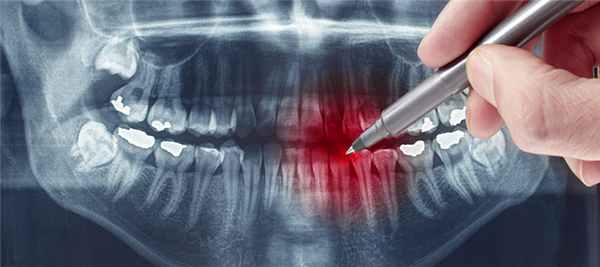

Рентгенограмма при конкресценции зубов

Рентген зубов: виды снимков, вред, противопоказания

Одним из традиционных и весьма популярных диагностических способов в стоматологической отрасли является рентгенологическое обследование. Что видно на рентгене зубов? Дентальный снимок позволяет определить степень поражения твердых тканей, выявить скрытый кариес, оценить качество ранее проведенного лечения зубов, а также своевременно диагностировать очаги воспаления в периодонте.

Снимки рентгена позволяют наглядно продемонстрировать не только состояние костных тканей, но и определить множество негативных изменений. Это крайне важно для постановки точного диагноза и определения соответствующей схемы лечения.

Ортопантомограмма (ОПТГ)

Это один видов исследования, пользующийся достаточным спросом. С помощью данной методики удается получить изображение абсолютно всех челюстей и зубов.

Что дает панорамный снимок зубов?

Полученное изображение дает специалисту следующие сведения:

- Наличие фибром и других новообразований.

- Скрытый кариес.

- Выявить непрорезавшиеся зубы и их точное положение.

- Выявить костные заболевания.

Другими показаниями к ОПТГ являются предстоящая процедура имплантации, запланированное хирургическое вмешательство, а также другие сложные манипуляции.